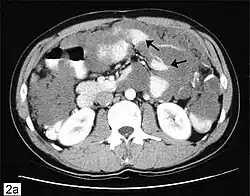

![]() Tomografía axial computarizada de abdomen que muestra la existencia de un pseudomixoma peritoneal con múltiples masas peritoneales señaladas por flechas. | ||